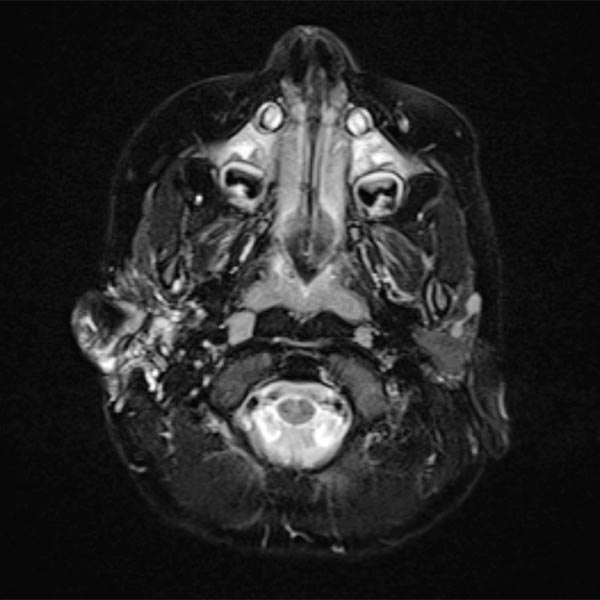

Transverse, T2-weighted, fat-saturated MRI 13 months after surgery. Only a few remnants of the lymphatic malformation are still visible.